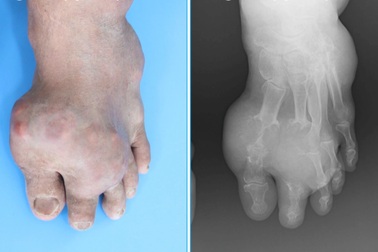

Bệnh gút được điều trị như thế nào?Bệnh gút từng được xem là "bệnh của người giàu", với chế độ ăn quá thịnh soạn. Nhưng loại bệnh viêm khớp phổ biến này, dẫn đến đau và sưng ở một hoặc nhiều khớp ảnh hưởng đến tất cả mọi người.

5 triệu chứng tố cáo bạn đã bị bệnh gút mạn tínhBệnh gút mạn tính là giai đoạn bệnh đã tiến triển nặng hơn. Nhận biết sớm những triệu chứng của bệnh gút sẽ giúp bạn có phương pháp điều trị và phòng ngừa biến chứng nguy hiểm.

Người mắc bệnh gút đang lạm dụng thuốc giảm đau“Gút là bệnh khớp hầu như có thể điều trị được, nhưng đã được điều trị cẩu thả nhất”. Hơn 60% bệnh nhân nhập viện đã chuyển sang giai đoạn gút mạn tính làm giảm chức năng gan, suy thận, loét dạ dày… nguyên nhân do dùng thuốc chống viêm, giảm đau kéo dài.